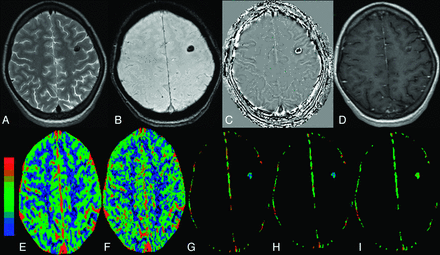

The colloidal stage of NCC with edema in the right frontal region in a 16-year-old girl who presented with recurrent partial seizures. A, The cyst appears hyperintense with a hypointense capsule on axial T2-FSE image. B, The cyst appears hypointense on FLAIR image with hyperintense perifocal edema. C, The lesion shows rim enhancement on a postcontrast T1-weighted image. D, Scolex is evident as an eccentric hypointense dot on SWAN image. E–I, On color-coded CBF [rCBF = 3.8 (E)], CBV [rCBV = 3.1 (F)], kep [kep = 1.5 minutes−1 (G)], Ktrans [Ktrans = 0.18 minutes−1 (H)], and ve [ve = 0.13 (I)] maps, the abnormal changes are clearly evident in and around the capsule of the lesion.

The colloidal stage of NCC is usually associated with intense perilesional inflammation and an increased breach in the BBB.15,16 This stage is associated with the development of seizures. Postcontrast study usually shows rim enhancement. MMP-9 expression is known to get up-regulated in inflammation and is associated with breakdown in the BBB.2,3,8,17 A link exists between the degree of inflammation and BBB breakdown. We observed the highest values of kep, Ktrans, and ve (Fig 1), which are the measures of BBB breakdown, in this stage of the disease. These changes are associated with maximal up-regulation of serum MMP-9 expression, which confirms that the inflammation is intense at this stage and shows the maximal breach in the BBB and correlates with it.